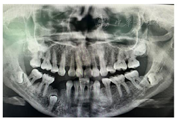

。CBCT示11牙根向远中明显弯曲,牙根发育至Nolla9期;21牙根发育至Nolla9期,腭侧见两颗正置锥形多生牙,牙根未发育完成;12、22牙根发育至Nolla9期;23牙冠近中倾斜至62根方。

根尖片示:11自根中向远中弯曲约35°,属Ⅱ类弯曲牙,牙根发育至Nolla9期,21牙根发育至Nolla9期,腭侧见两颗正置锥形多生牙;12、22牙根发育至Nolla9期。

CBCT示:上颌恒牙胚萌出间隙不足,根据Moyers混合牙列分析法,牙弓现有长度为177.4 mm,牙弓应用长度为181.6 mm,拥挤度为4.2 mm。42缺失;11、21、22发育至Nolla9期;55、16、65、46冠部低密度影及牙本质中层,根管内未见高密度充填影,根尖周未见明显异常。53、63牙根吸收不足1/3,13、23发育至Nolla8期。